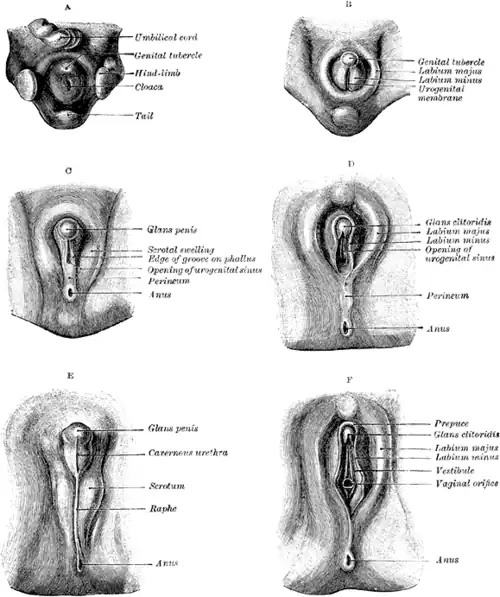

In week three of the development of the embryo, mesenchyme cells from the primitive streak migrate around the cloacal membrane.[37] Early in the fifth week, the cells form two swellings called the cloacal folds.[38] The cloacal folds meet in front of the cloacal membrane and form a raised area known as the genital tubercle.[38][37] The urorectal septum fuses with the cloacal membrane to form the perineum. This division creates two areas one surrounded by the urethral folds and the other by the anal folds.[38][37] These areas become the urogenital triangle and the anal triangle.[2] The area between the vulva and the anus is known as the clinical perineum.[2]

At the same time, a pair of swellings on either side of the urethral folds known as the genital swellings develop into the labioscrotal swellings.[38][37] Sexual differentiation takes place, and at the end of week 6 in the female, hormones stimulate further development and the genital tubercle bends and forms the clitoris.[38][37] The urethral folds form the labia minora and the labioscrotal swellings form the labia majora. At this time, the sexes still cannot be distinguished.[37] The appearance of the external genitalia is similar in male and female embryos until the twelfth week and even then is difficult to distinguish.[38]

The uterovaginal canal or genital canal, forms in the third month of the development of the urogenital system. The lower part of the canal is blocked off by a plate of tissue, the vaginal plate. This tissue develops and lengthens during the third to fifth months and the lower part of the vaginal canal is formed by a process of desquamation or cell shedding. The end of the vaginal canal is blocked off by an endodermal membrane which separates the opening from the vestibule. In the fifth month, the membrane degenerates but leaves a remnant called the hymen.[38]

Organs in the male and female with a shared common ancestry are said to be homologous.[2] The clitoral glans is homologous to the male glans penis,[21] and the clitoral body is homologous to the shaft of the penis.[39] The labia majora are homologous to the scrotum;[2] the clitoral hood is homologous to the foreskin,[14] and the labia minora are homologous to the penile raphe.[1][40][41] The vestibular bulbs beneath the skin of the labia minora are homologous to the corpus spongiosum, the tissue of the penis surrounding the urethra, and to the bulb of the penis.[1] Bartholin's glands are homologous to the bulbourethral glands in males.[2]